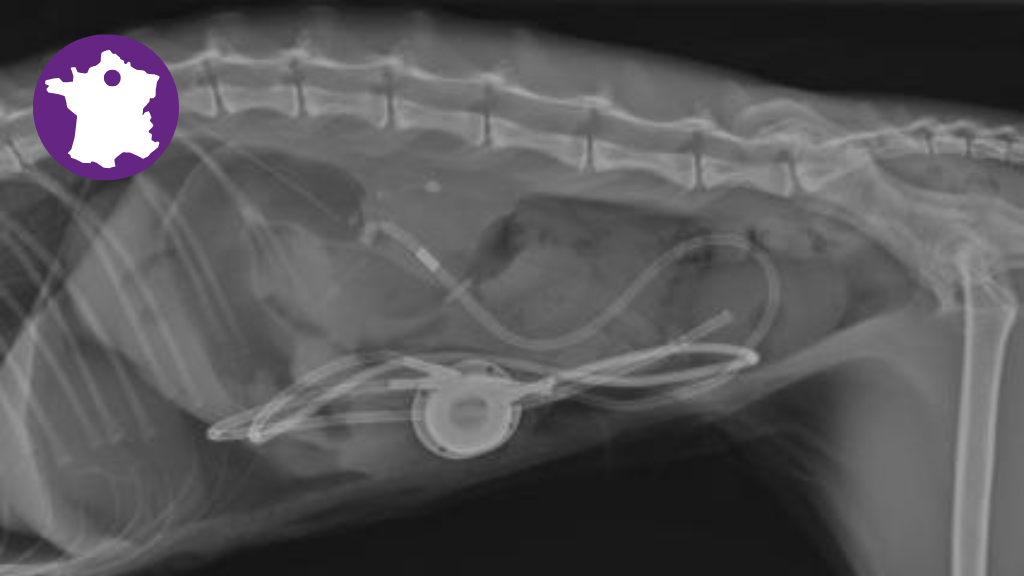

- Connaître les indications, risques et contre-indications de la mise en place chirurgicale d'un dispositif de dérivation pyélovésicale extraurétérale chez le chat,

- Prendre en charge chirurgicalement un chat présentant une obstruction urétérale en mettant en place une dérivation pyélovésicale extraurétérale, et en réaliser le suivi post-opératoire à court et long termes

Programme type